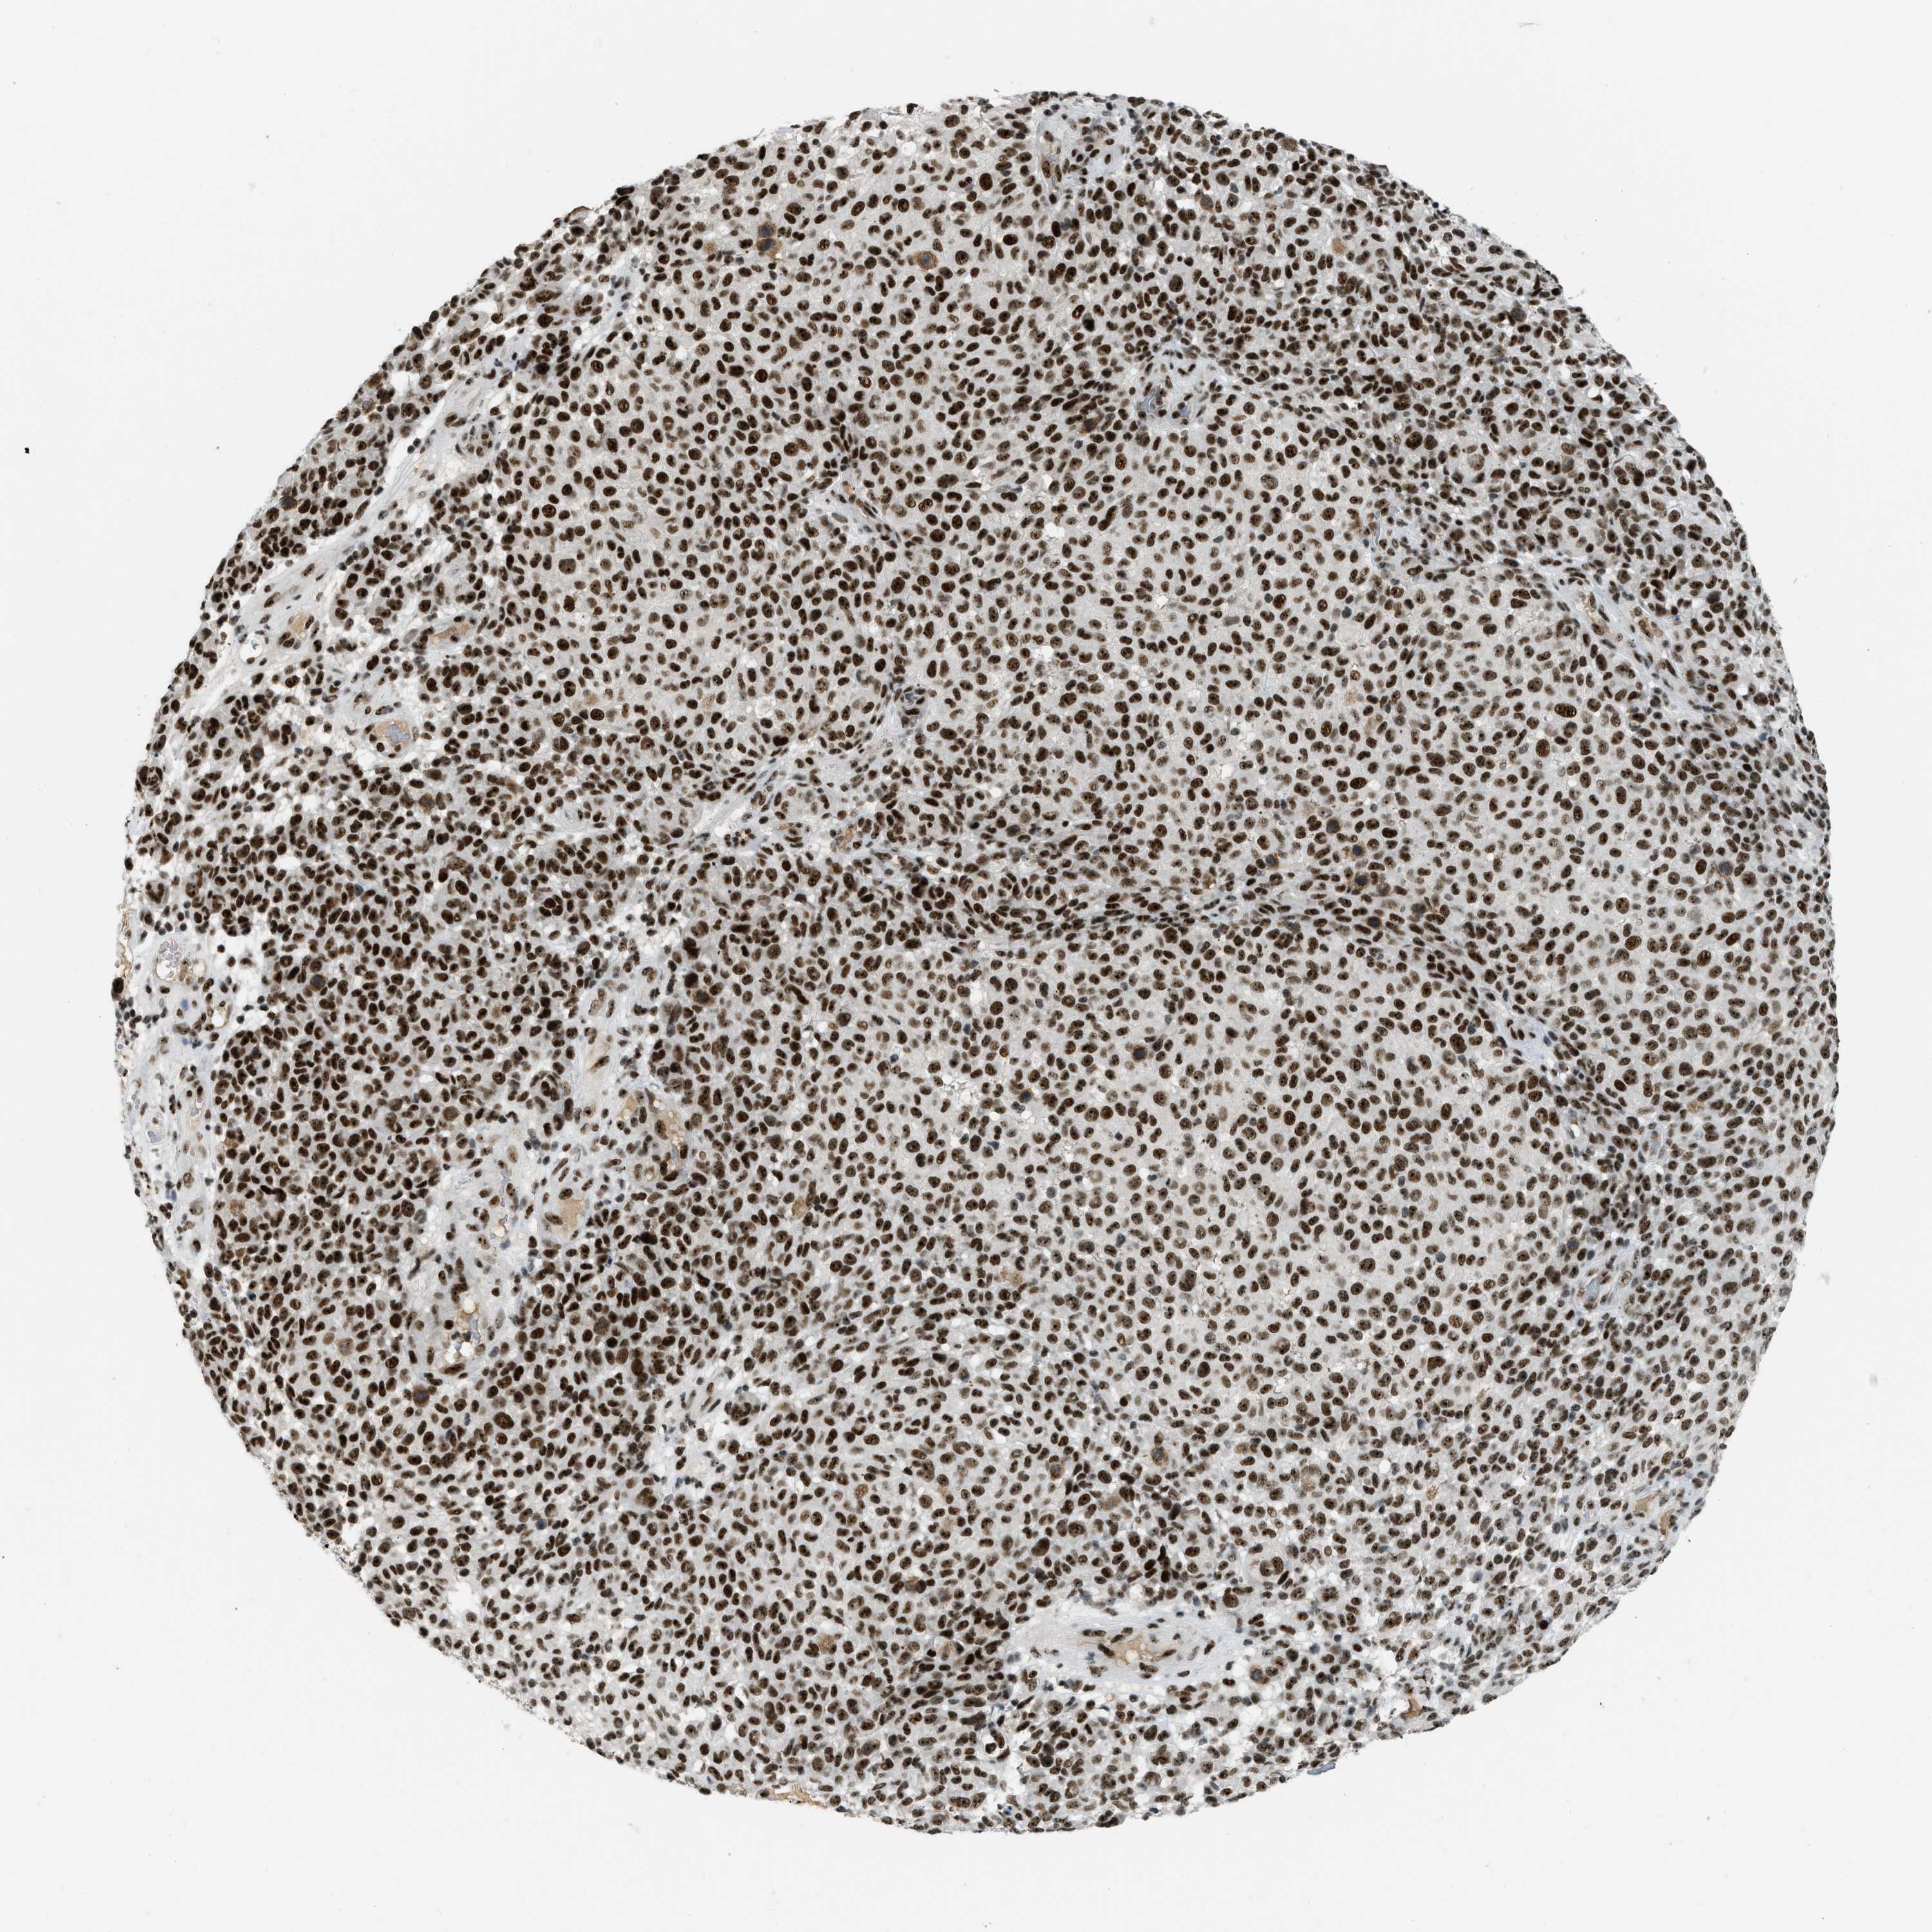

MELANOMA - Protein expressioni

A mouse-over function shows sample information and annotation data. Click on an image to view it in a full screen mode. Samples can be filtered based on level of antibody staining by selecting one or several of the following categories: high, medium, low and not detected. The assay and annotation is described here.

Note that samples used for immunohistochemistry by the Human Protein Atlas do not correspond to samples in the TCGA dataset.

Antibody stainingi

Antibody staining in the annotated cell types in the current human tissue is reported as not detected, low, medium, or high, based on conventional immunohistochemistry profiling in selected tissues. This score is based on the combination of the staining intensity and fraction of stained cells.

Each image is clickable and will lead to virtual microscopy that enables deeper exploration of all samples and also displays staining intensity scores, fraction scores and subcellular localization as well as patient and tissue information for each sample.

Antibody HPA018334

Staining

High

Medium

Low

Not detected

Intensity

Strong

Moderate

Weak

Negative

Quantity

>75%

75%-25%

<25%

None

Location

Nuclear

Cytoplasmic/membranous

Cytoplasmic/membranous,nuclear

Malignant melanoma, NOS

Malignant melanoma, Metastatic site